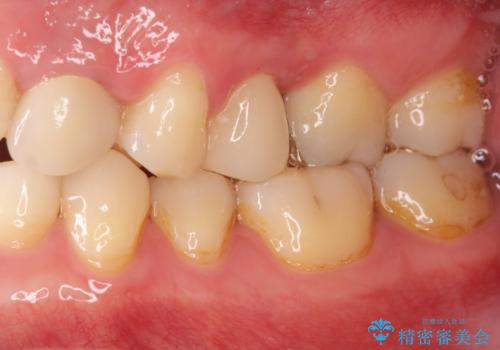

90°ねじれてしまっていた歯を、矯正治療で治し、前後の歯の咬合関係も改善してしっかりと噛めるようになりました。